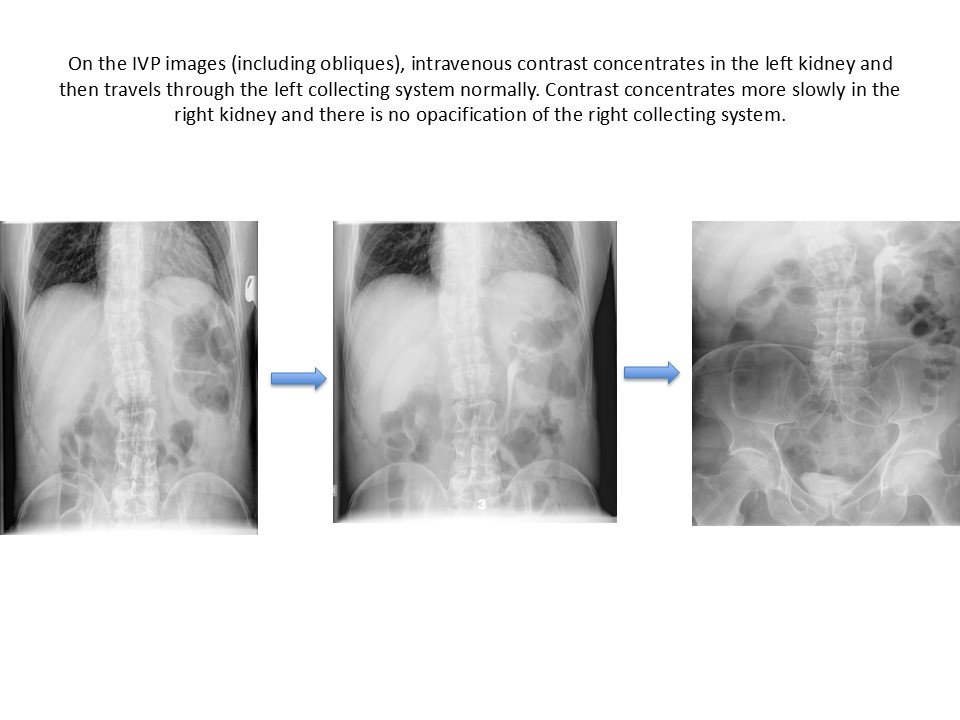

The right kidney and ureter were not visualized on intravenous urography until 60 min. The left kidney and ureter revealed normal.

On the 20 min post-void image there is opacification of the right kidney (delayed nephrogram), still without any contrast in the collecting system, compatible with high-grade obstruction of the right collecting system.